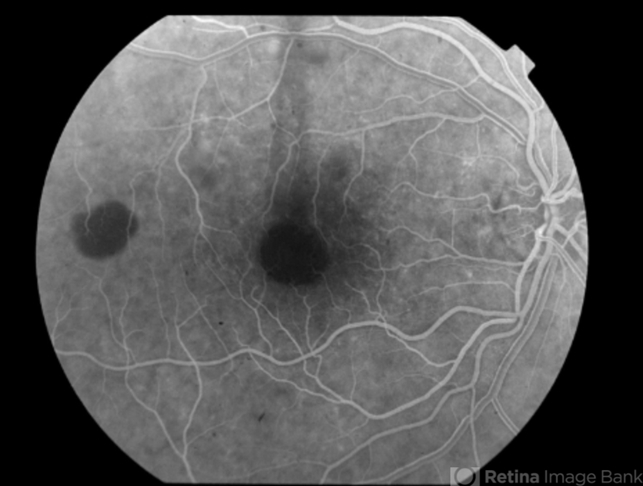

- Multifocal Best Disease

- Best disease, adult vitelliform dystrophy

- Angiography reveals blocking defects due to pigment clumping with no evidence of CNVM.